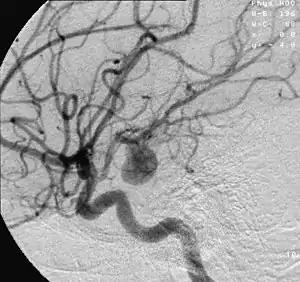

- Focal cerebral ischemia – A stroke occurring in a localized area that can either be acute or transient. This may be due to a variety of medical conditions such as an aneurysm that causes a hemorrhagic stroke, or an occlusion occurring in the affected blood vessels due to a thrombus (thrombotic stroke) or embolus (embolic stroke).[20] Focal cerebral ischemia constitutes a large majority of the clinical cases in stroke pathology with the infarct usually occurring in the middle cerebral artery (MCA).[21]